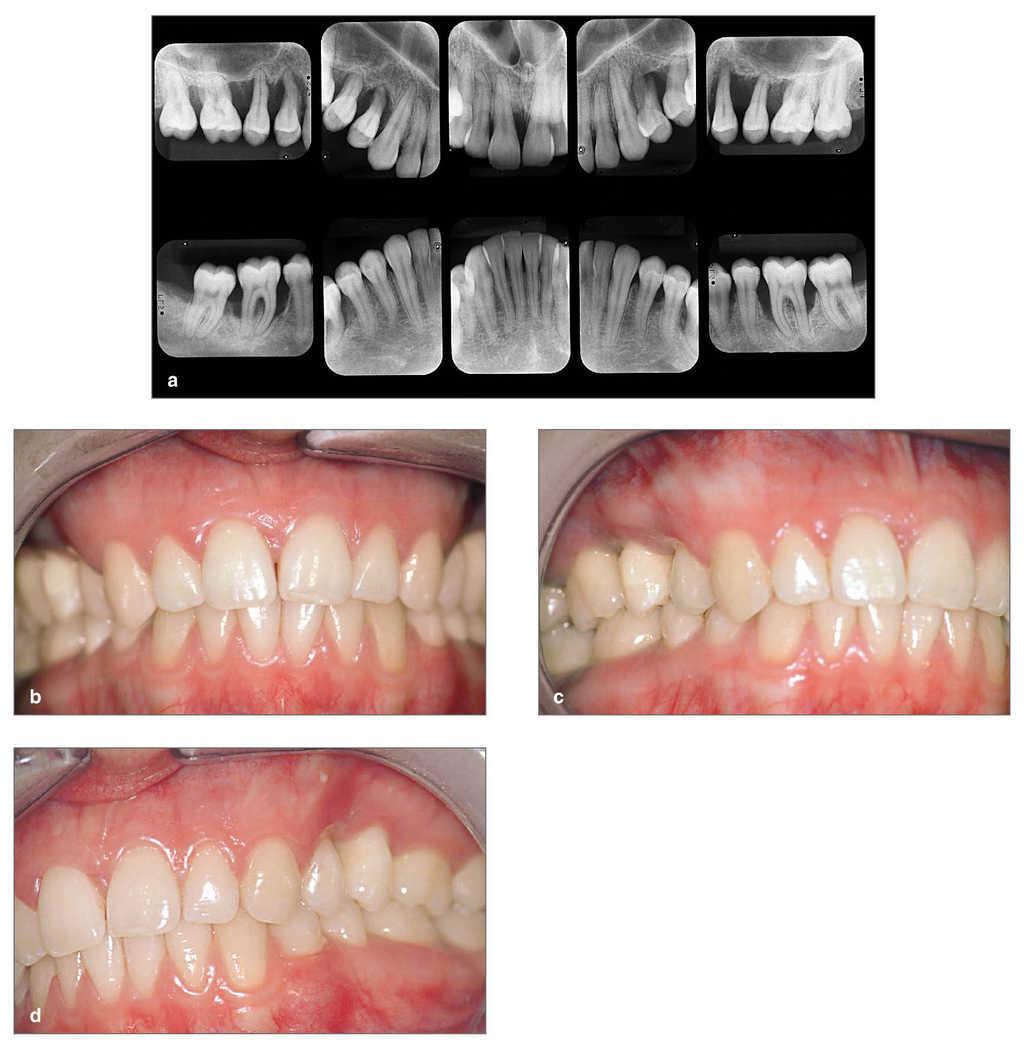

En la primera visita a nuestra clínica dental en el año 2000, cuando la paciente contaba con 23 años de edad (figs. 2a a 2d), resultaba muy dudosa la posibilidad de preservar los premolares superiores debido a la avanzada destrucción periodontal. Los hallazgos clínicos y radiográficos indicaron una periodontitis agresiva severa1.

Figuras 2a a 2d. Estado radiográfico detallado y situación clínica en el año 2000 antes del tratamiento periodontal quirúrgico y no quirúrgico sistemático.